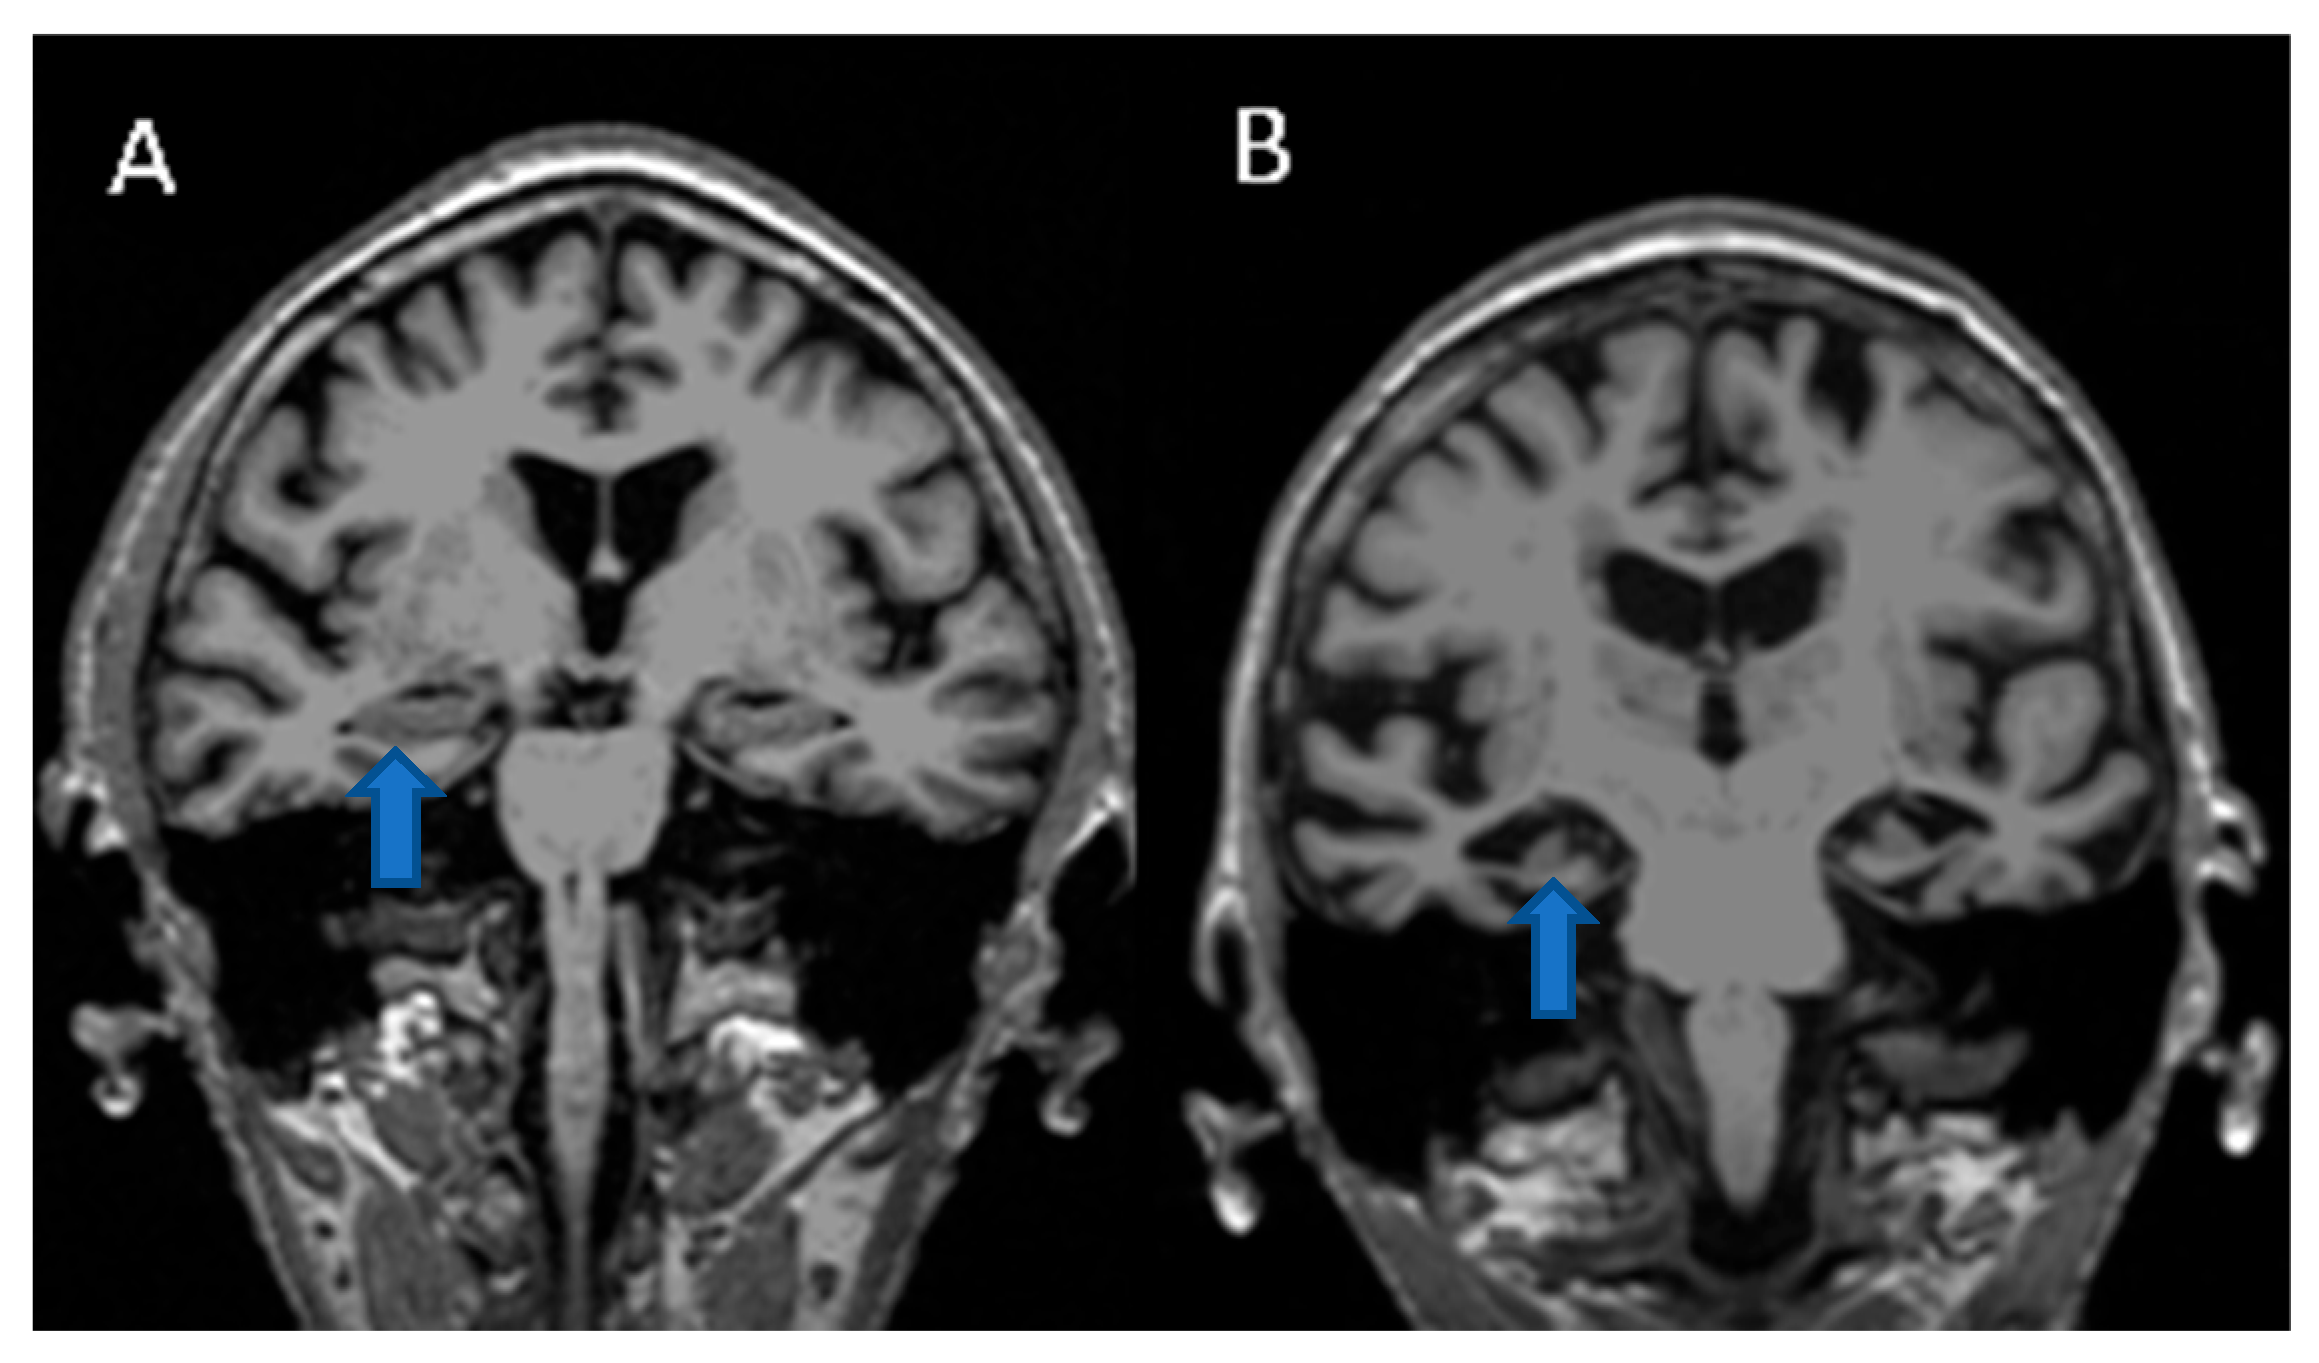

2.1. MRI Imaging of the Hippocampus of a Control Patient vs. An Alzheimer’s Disease Patient